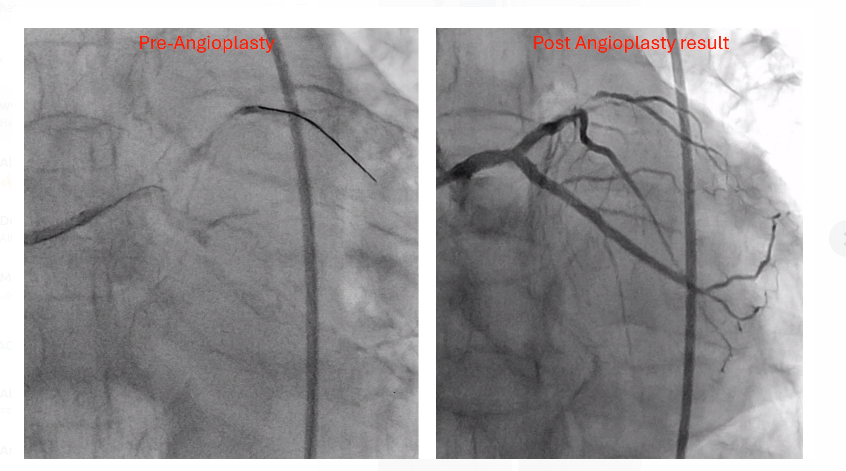

Life-Saving Angioplasty by Dr. Hasmukh Gujar in Pune

Dr. Hasmukh Gujar, Consultant Interventional Cardiologist in Pune, recently performed a life-saving angioplasty where a seemingly small artery, once t...